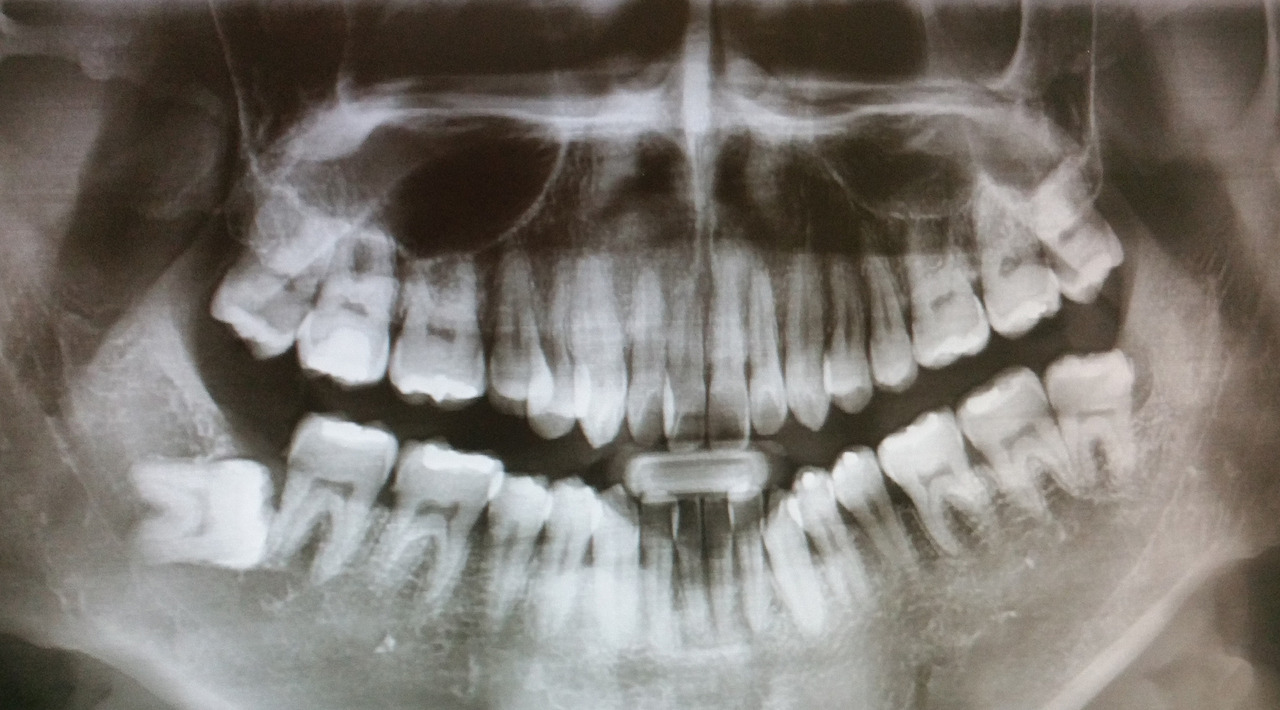

dr17071001.jpg좌측 위아래, 우측 위 사랑니를 뽑았다. 우측 아래 사랑니는 뽑기도 어렵고 잇몸 속에 있어서 불편함이 없으면 그냥두고 정기 검진을 통해 지켜보자고 한다.

치과를 방문할수록 신뢰는 깊어졌고 드디어 사랑니를 뽑는 날이다. 총 4개의 사랑니 중 우측 아래는 완전히 옆으로 누워있었는데, 잇몸 속에 있고 특별한 증상이 없으니 그냥 두자고 했다. 다행이다. 엑스레이만 봐도 이건 보통 일이 아니라는 것을 알 수 있다. 좌측 위아래를 뽑고 일주일 후 우측 위를 뽑기로 했다.